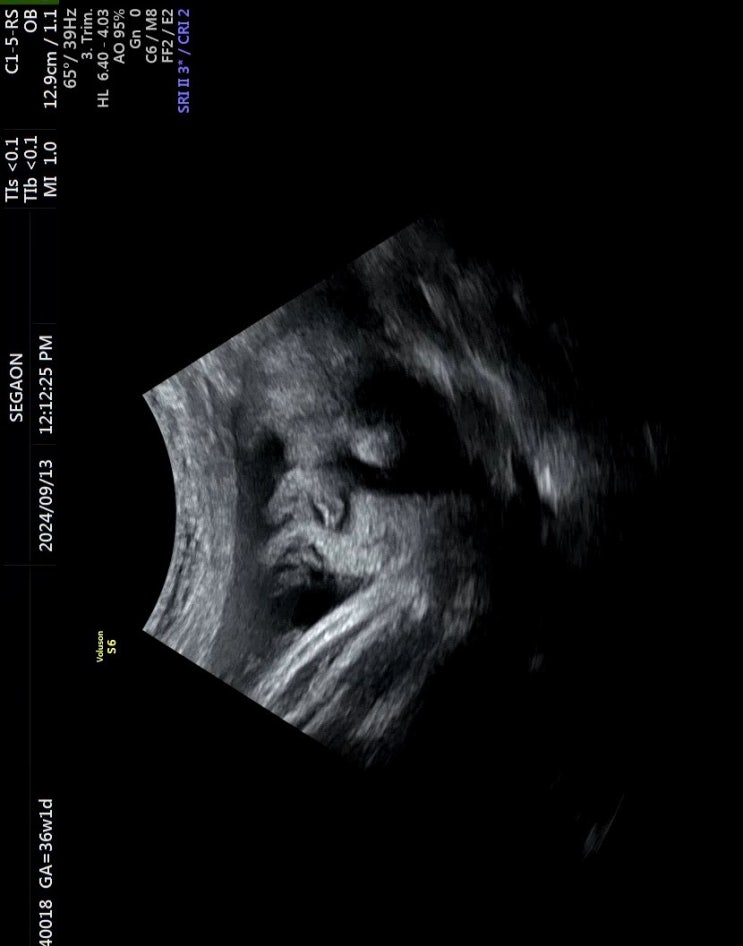

임산부 코로나 / 막달 검사 / 세가온 산부인과 태동 검사

8월 27일 33주 5일차 산부인과 검진 전날 감기인지 몸살인지 38도 열이 남... ㅜㅜ 감기로 예전에 산부인과...